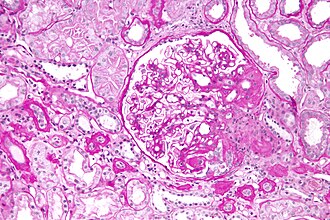

Etiologija ili incijalni mehanizam nastanka bolesti je još velikim dijelom nepoznat, osim u određenim slučajevima bolesti uzrokovanih virusima. Primarni patofiziolški proces je oštećenje u blizini ili izravno podocita, brisanje nastavka nožica, proliferacija mezangija, endotelnih i epitelnih stanica u ranoj fazi, nakon koje slijedi smanjivanje i kolaps glomerularnih kapilara, te na kraju nastanak ožiljka (skleroza - nakupljanje kolagena tip IV, a ponekad hijalinoza - nakupljanje hijalina). Karakteristična lezija je segmentalna solidifikacija glomerula, najčešće perihilarne regije, a ponekad i perifernije, uključujući i tubule. Stupanj oštećenja različite je za pojedina područja u bubregu, od normalnih nezahvaćenih glomerula do segmentalne, te konačne globalne glomeruloskleroze. Postoji određeni podtipovi bolesti, koji se morfološki razlikuju.